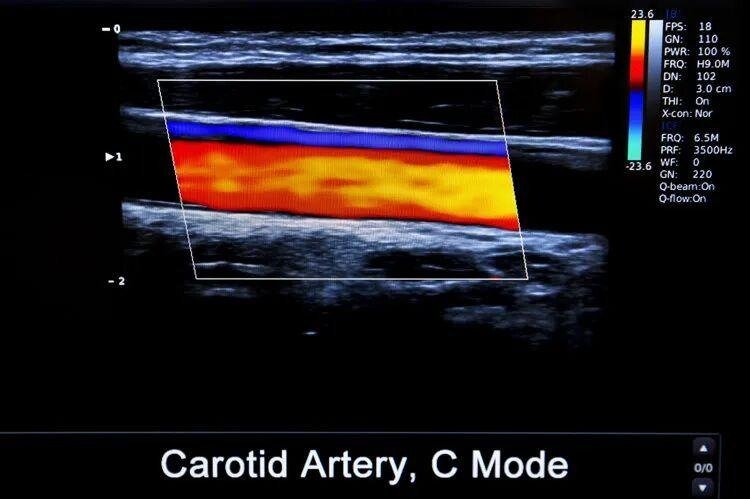

血栓栓塞是由于动/静脉内形成了血凝块导致的潜在性致死性疾病。血栓会在血管内随着血液循环不断游离,在任何年龄、任意时间都可能发生,一旦堵塞血管,会导致全身的血液循环系统瘫痪,导致细胞死亡,威胁全身健康。

血栓根据发生部位的不同以及表现可分为心脏血栓、静脉血栓和动脉血栓,不同血栓容易堵塞的部位不同。

• 动脉血栓:最容易堵塞心脏,这是十分凶险的病症。一旦凝固的血块堵住血管,会导致组织器官没有血液供应,从而诱发心梗、脑梗,没有及时抢救会导致患者死亡。

• 静脉血栓:静脉血栓很容易堵塞肺部,在早期静脉血栓生成的时候身体可能没有任何症状和感觉,但一旦发病就可能会致命。